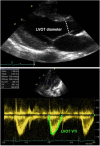

In the neonatal and pediatric intensive care setting, bedside cardiac ultrasound is often used to assess ventricular dimensions and function. Depending upon the underlying disease process, it is necessary to be able to evaluate the systolic and diastolic function of left and or right ventricles. The systolic function of left ventricle is mostly assessed qualitatively on visual inspection "eye-balling" and quantitatively by measuring circumferential fraction shortening or calculating the ejection fraction by Simpson's planimetry. The assessment of left ventricular diastolic function relies essentially on the mitral valve and pulmonary venous Doppler tracings or tissue Doppler evaluation. The right ventricular particular shape and anatomical position does not permit to use the same parameters for measuring systolic function as is used for the LV. Tricuspid annular plane systolic excursion (TAPSE) and S' velocity on tissue Doppler imaging are more often used for quantitative assessment of right ventricle systolic function. Several parameters proposed to assess right ventricle systolic function such as fractional area change, 3D echocardiography, speckle tracking, and strain rate are being researched and normal values for children are being established. Diastolic function of right ventricle is evaluated by tricuspid valve and hepatic venous Doppler tracings or on tissue Doppler evaluation. The normal values for children are pretty similar to adults while normal values for the neonates, especially preterm infants, may differ significantly from adult population. The normal values for most of the parameters used to assess cardiac function in term neonates and children have now been established.